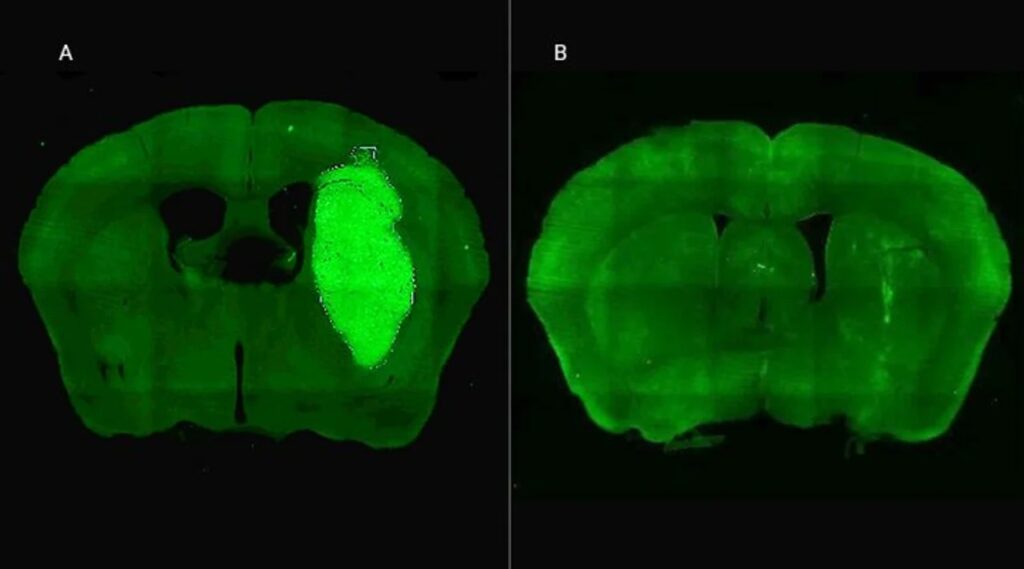

Candolfi y colegas utilizaron una terapia génica experimental basada en una molécula muy pequeña o péptido llamado P60, desarrollado por Juan José Lasarte en la Universidad de Navarra, en España, que atraviesa la membrana celular e inhibe la proteína Foxp3. «Cuando en experimentos de laboratorio bloqueamos Foxp3 utilizando P60, la respuesta de las células de glioblastoma a la radioterapia y a una variedad de drogas quimioterapéuticas mejoró notablemente», destacó la investigadora del CONICET.

Además, P60 tuvo efectos antitumorales directos, reduciendo la viabilidad y la migración de las células de glioblastoma e inhibiendo la proliferación de células endoteliales que son clave para la progresión del tumor. Para evaluar estos efectos, los autores del estudio utilizaron una variedad de modelos celulares murinos (de roedor) y humanos. «En particular, los cultivos derivados de biopsias de pacientes con glioblastoma desarrollados por nuestro colaborador Guillermo Videla Richardson, del Instituto FLENI, son muy útiles para representar la heterogeneidad de estos tumores», indicó Candolfi.